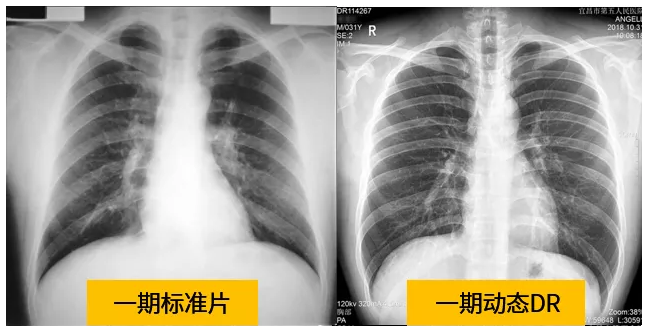

動態(tài)dr的拍攝效果圖

動態(tài)DR技術(shù)與普通DR單截面診斷的不同就是在操作過程中,可以隨時切換成透視模式,透視/攝片模式實時切換,對陰影進行多角度動態(tài)的鑒別。實時點片、實時回放、連續(xù)點片等多功能大大的增加了初診的準(zhǔn)確率。在小陰影的形態(tài)和性質(zhì),特別是不規(guī)則小陰影的判斷方面提升,從而達到提高胸片整體判斷準(zhǔn)確性。

根據(jù)數(shù)據(jù)統(tǒng)計表現(xiàn),利用動態(tài)dr進行檢查的話,圖像的質(zhì)量和輻射劑量相對較少。并且動態(tài)DR在圖像清晰度和射線穿透力方面完全能達到塵肺診斷的要求。這種檢查效果的精準(zhǔn)和便捷性是和普通設(shè)備不一樣的,動態(tài)DR塵肺攝影應(yīng)用于塵肺疾病診斷中,可以提高檢出率及優(yōu)片率。